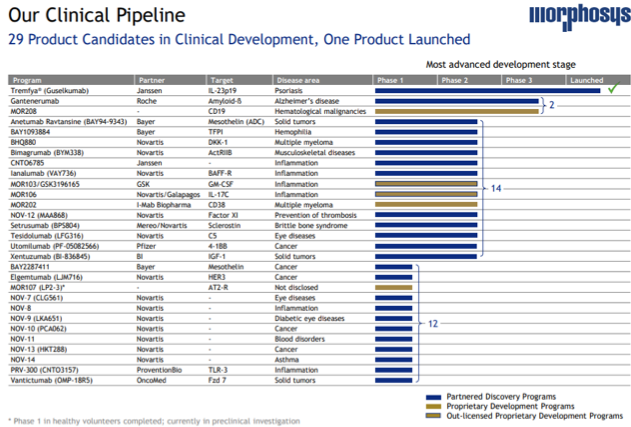

This biotechnology company is a pioneer in field of therapeutic antibodies and has an innovative proprietary technology platform based on antibody capabilities and peptide formats. Its lead product candidate MOR208, a lenalidomide combination in relapsed/refractory diffuse large B cell lymphoma (r/r DLBCL) has been awarded a breakthrough therapy designation by the FDA. The company boasts of a vast pipeline of products consisting of over 29 product candidates by virtue of various proprietary and partnership agreements.

The company has built a robust partnership and collaboration network to achieve growth and advancement in multiple areas such as cancer, psoriasis, alzheimer’s solid tumors, hemophilia and inflammation to name a few.

Its proprietary development pipeline consists of its lead product candidate MOR208 targeted at DLBCL (B-MIND) and is in phase III clinical trials, while its MOR107 for oncology is in preclinical stage. It is developing MOR202 for multiple myeloma in partnership with I-Mab Biopharma for development in China, Hong Kong, Macau, Taiwan and South Korea (MOR210 only) and MOR210 for oncology applications, the company has received a $20 million upfront and is eligible for another $100 million in milestone payments and tiered double-digit royalties.

It has collaboration with Novartis (NYSE:NVS)/Galapagos (NASDAQ:GLPG) for development of MOR106 for treatment of atopic dermatitis for which the company has received EUR 95 million and will receive an estimated EUR 850 million in milestone payment in the future along with royalties.

It is also developing MOR103 /GSK3196165, an anti – GM-CSF antibody for inflammatory diseases in a full out-licensed agreement with GSK in lieu of EUR 22.5 million upfront payment and potential milestone payments of EUR 423 million and royalties.